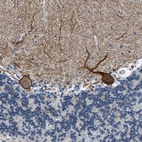

Immunohistochemical staining of human cerebellum shows strong membranous positivity in Purkinje cells.